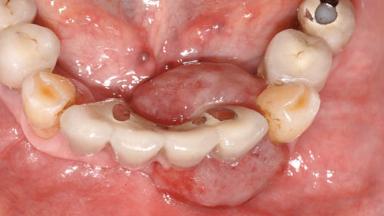

Peripheral Giant-cell Granuloma Associated with Peri-implant Tissues

# of Teeth 10

# of Implants 5

Type of Implants One-Piece